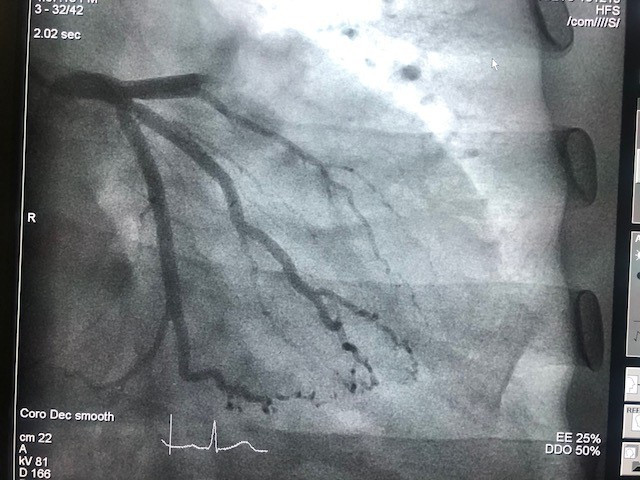

Theo ThS. BS Trần Hòa (Phó trưởng khoa tim mạch can thiệp BV ĐH Y Dược TPHCM), ngay sau khi tiếp nhận bệnh nhân, các BS đã tiến hành can thiệp động mạch vành cấp cứu cho người bệnh. Tại đơn vị can thiệp nội mạch của BV, kết quả chụp động mạch vành cho thấy đoạn giữa động mạch vành bên phải của bệnh nhân bị tắt hoàn toàn. Bệnh nhân được tái thông và đặt stent vào nơi sang thường bị tắt nghẽn, hiện sức khỏe bệnh nhân đã ổn định. “Nếu can thiệp trễ, bệnh nhân sẽ dẫn đến tình trạng nhịp chậm, ngất có thể tái phát dần chuyển đến ngưng tim và tử vong”, BS Hòa cho biết